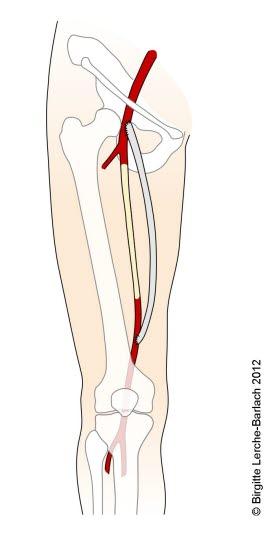

Kirurgi med blokking av trange partier i blodåren, eller utskifting av blodårer (by-pass), kan i noen tilfeller være nødvendig for å lindre plager. Slik behandling er imidlertid ikke livsforlengende. Operasjon gjøres kun der alle behandlingsalternativer er forsøkt uten tilstrekkelig effekt. Operasjon er også nødvendig dersom det er akutt fare for koldbrann.